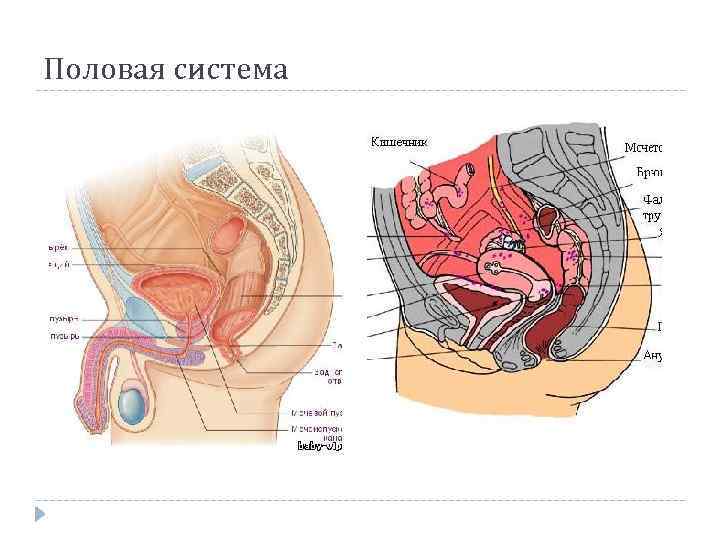

Половая система

Половая система

Топография малого таза

Топография малого таза